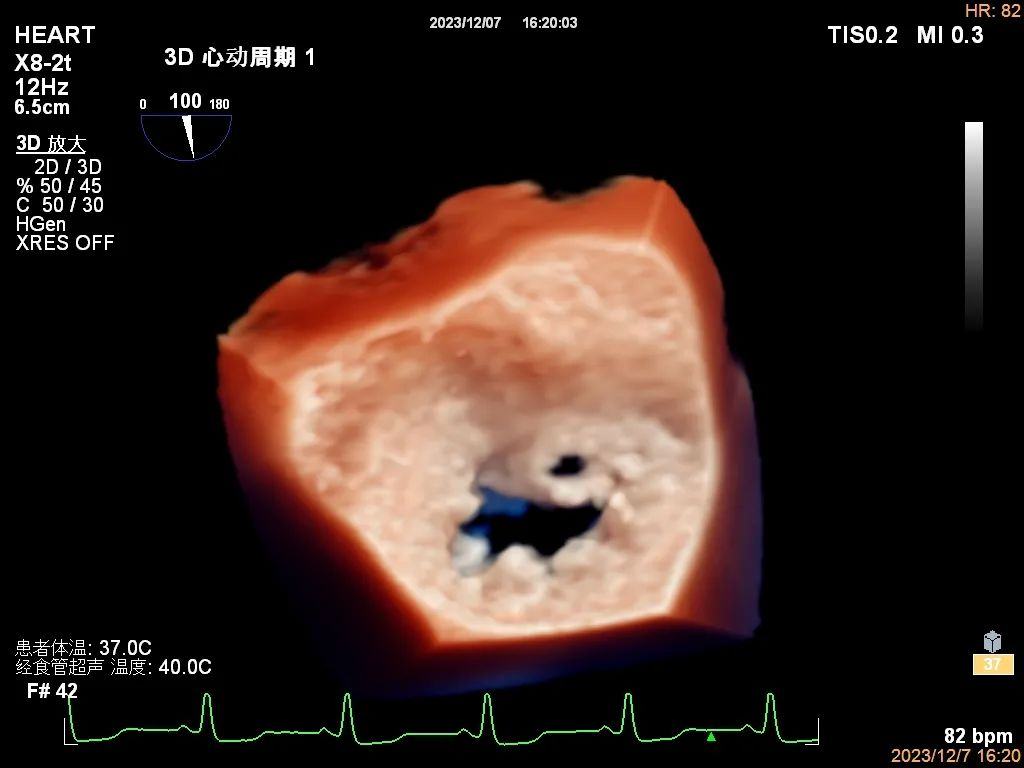

1、心脏自体瓣膜病变:如感染性心内膜炎、瓣膜返流及狭窄的病因诊断、瓣膜脱垂的病因及定位诊断等。

感染性心内膜炎二尖瓣前叶穿孔三维图